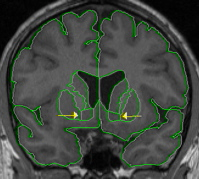

Segmentation: Nucleus Accumbens

| General Description  The nucleus accumbens is bordered superiorly by the internal capsule, caudate, and putamen. It is bordered inferiorly by white matter, or in its most posterior extent by the subcallosal gyrus. Its medial border is the septal nuclei, or lateral ventricle. Laterally it is bordered by the putamen. Because the nucleus accumbens is nearly impossible to see in a standard MRI, the CMA has come up with a convention for the segmentation of this structure. | |

|  | Part I - Caudate and putamen are discontinuous

|  | Part II - Caudate and putamen are continuous When caudate and putamen are connected, an oblique line should be drawn from the inferior most tip of the lateral ventricle to the inferior most tip of the internal capsule (the white matter area between the caudate and putamen). If the white matter tip is an "island" it should be connected with a line to the rest of the internal capsule and the division lines should be drawn with the "island" as the reference. Adjust the intensity contour to clearly see the full extent of white matter, to it's most inferior extent. This line will create the border between the caudate and the accumbens. From this point, a straight, vertical line should be drawn to provide the border between accumbens and putamen. The accumbens should end a slice or two in front of anterior commissure. |